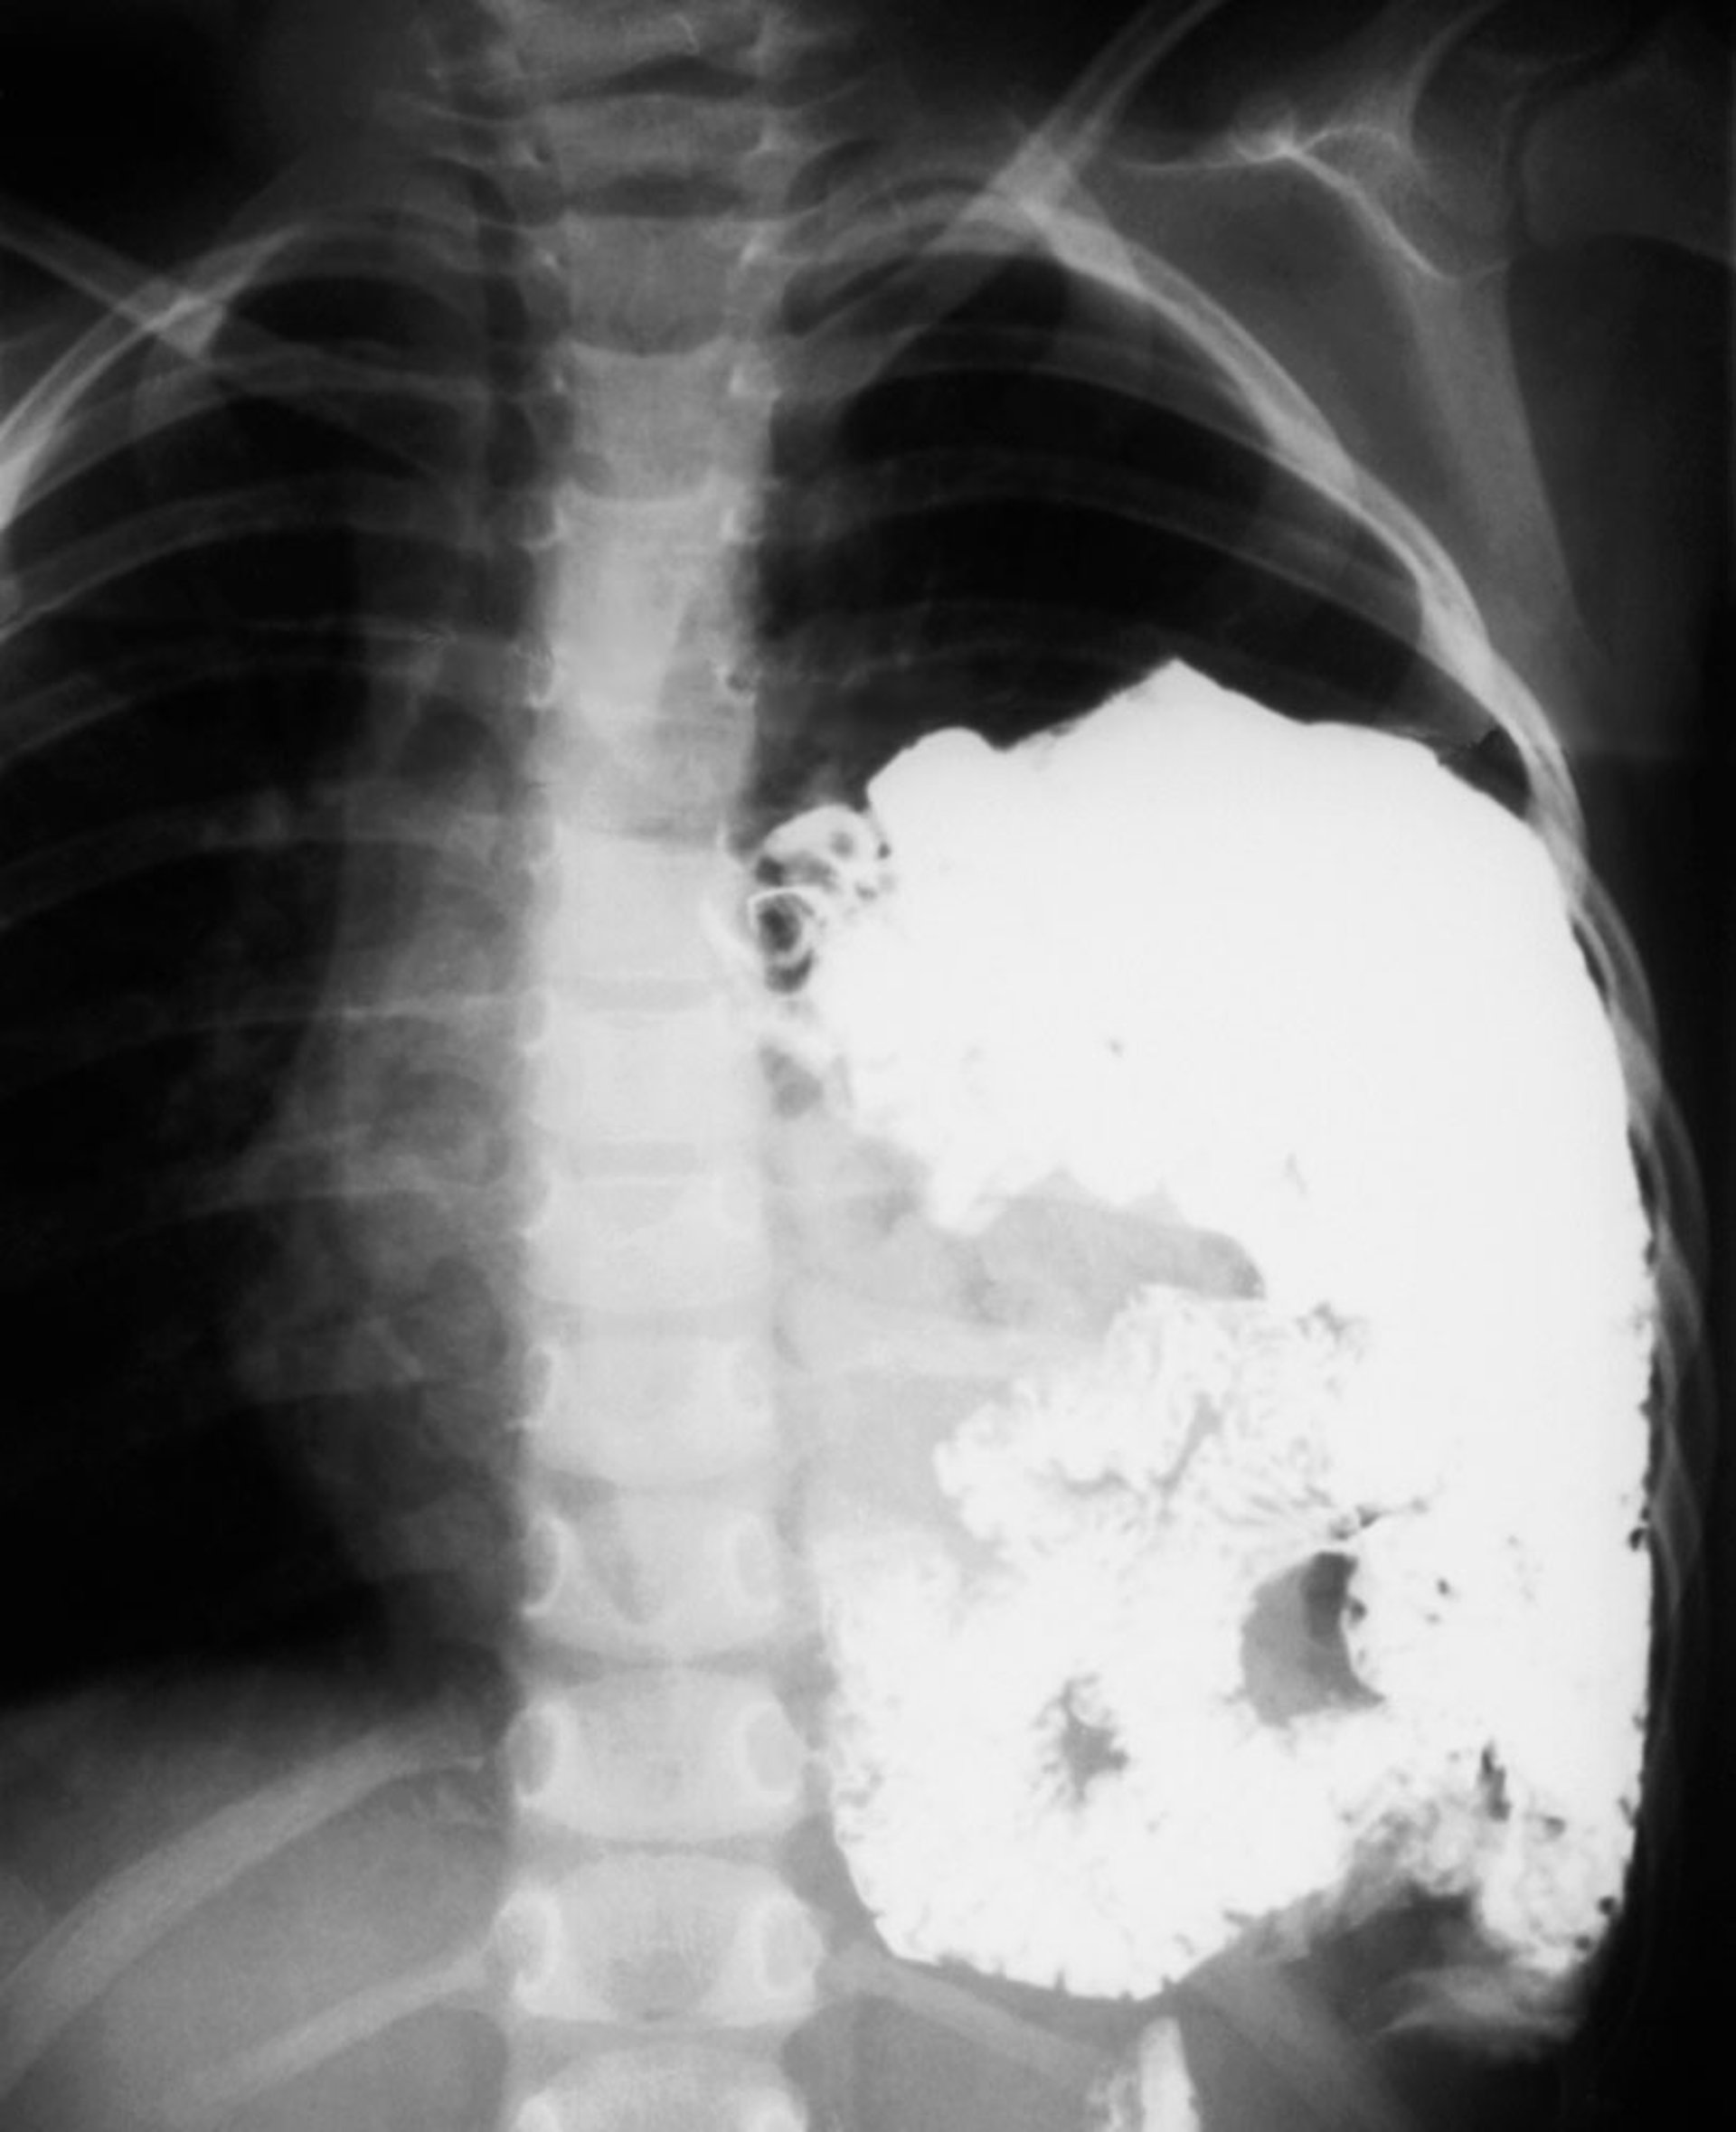

膈疝 (2)

在这项对比研究中,胃和肠道可见于左胸。

ZEPHYR/SCIENCE PHOTO LIBRARY